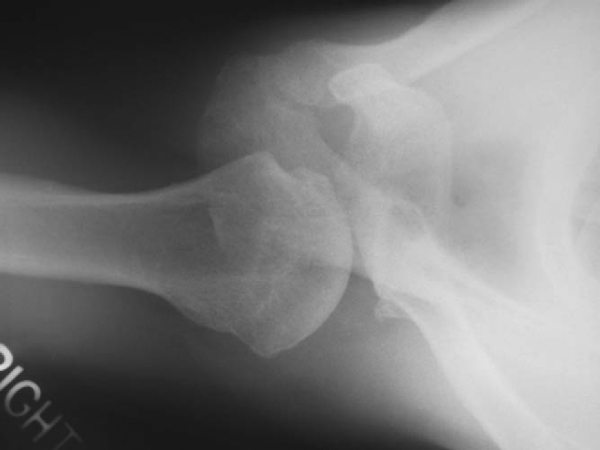

| • | Evaluate for reverse Hill-Sachs lesions ( Fig. 8-4 ), glenoid pathologic changes (retroversion, fractures, and hypoplasia), bony humeral avulsion of the glenohumeral ligaments |